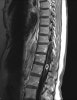

MRI : 척추의 전이성 종양(Metastatic tumor)